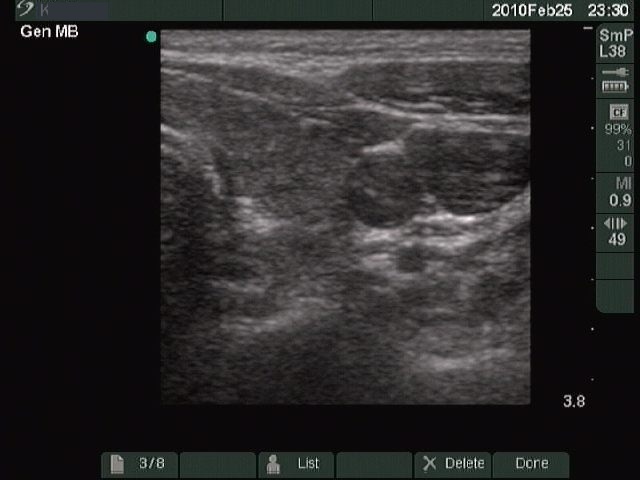

Chronic lymphocytic thyroiditis - Case 49. |

Clinical presentation: a 49-year-old woman with a newly discovered hypothyroidism (TSH 31.7 mIU/L) and a thyroid nodule in a previous sonographic report.

Ultrasonography: typical picture of Hashimoto's thyroiditis without any nodules.

Cytological report: benign Hashimoto's thyroiditis.